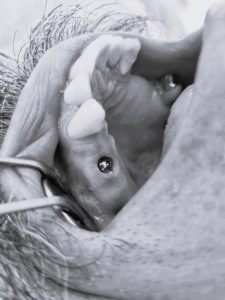

Anstatt das Zahnfleisch weiträumig aufzuschneiden, wird lediglich mit einer kleinen Stanze etwas Zahnfleisch abgetragen und anschließend ein Loch in den Knochen gebohrt.

Schließlich wird das passende Implantat eingebracht, womit automatisch das Stanzloch verschlossen und folglich eine offene Operationswunde komplett vermieden wird.

Die Operation dauert pro Implantat selten länger als 10 bis 15 Minuten und durch das Wegfallen einer offenen Operationswunde sind auch keine Nähte erforderlich und Schmerzen oder Schwellungen treten nur in den seltensten Fällen auf.